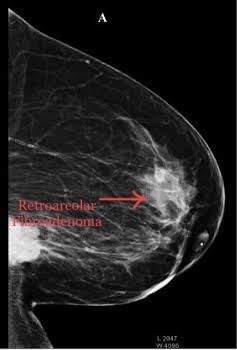

Retroareolar Fibroadenoma It accounts 8% of all breast cancers. Location: It is located at less than 2cm from the nipple or nipple-areolar conplex. Diagnosis: Is usually made by mammogram or Ultrasound. Fibroadenoma: They are breast lumps, and are not serious and is non cancerous. Evaluation is necesssary inorder to find whether it is benign or malignant. Fibroadenomas are removed only if they keep growing or changing shape. Sometimes these tumors stop growing or even shrink on their own without any treatment.